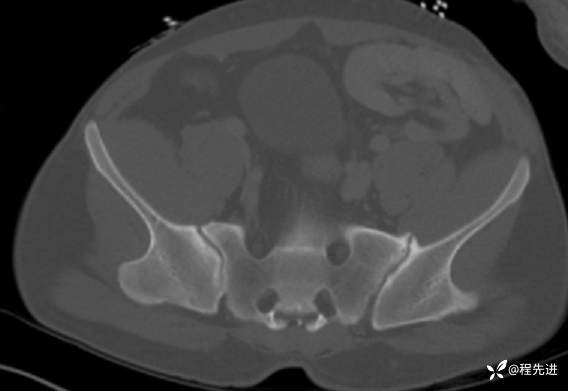

CT:

img